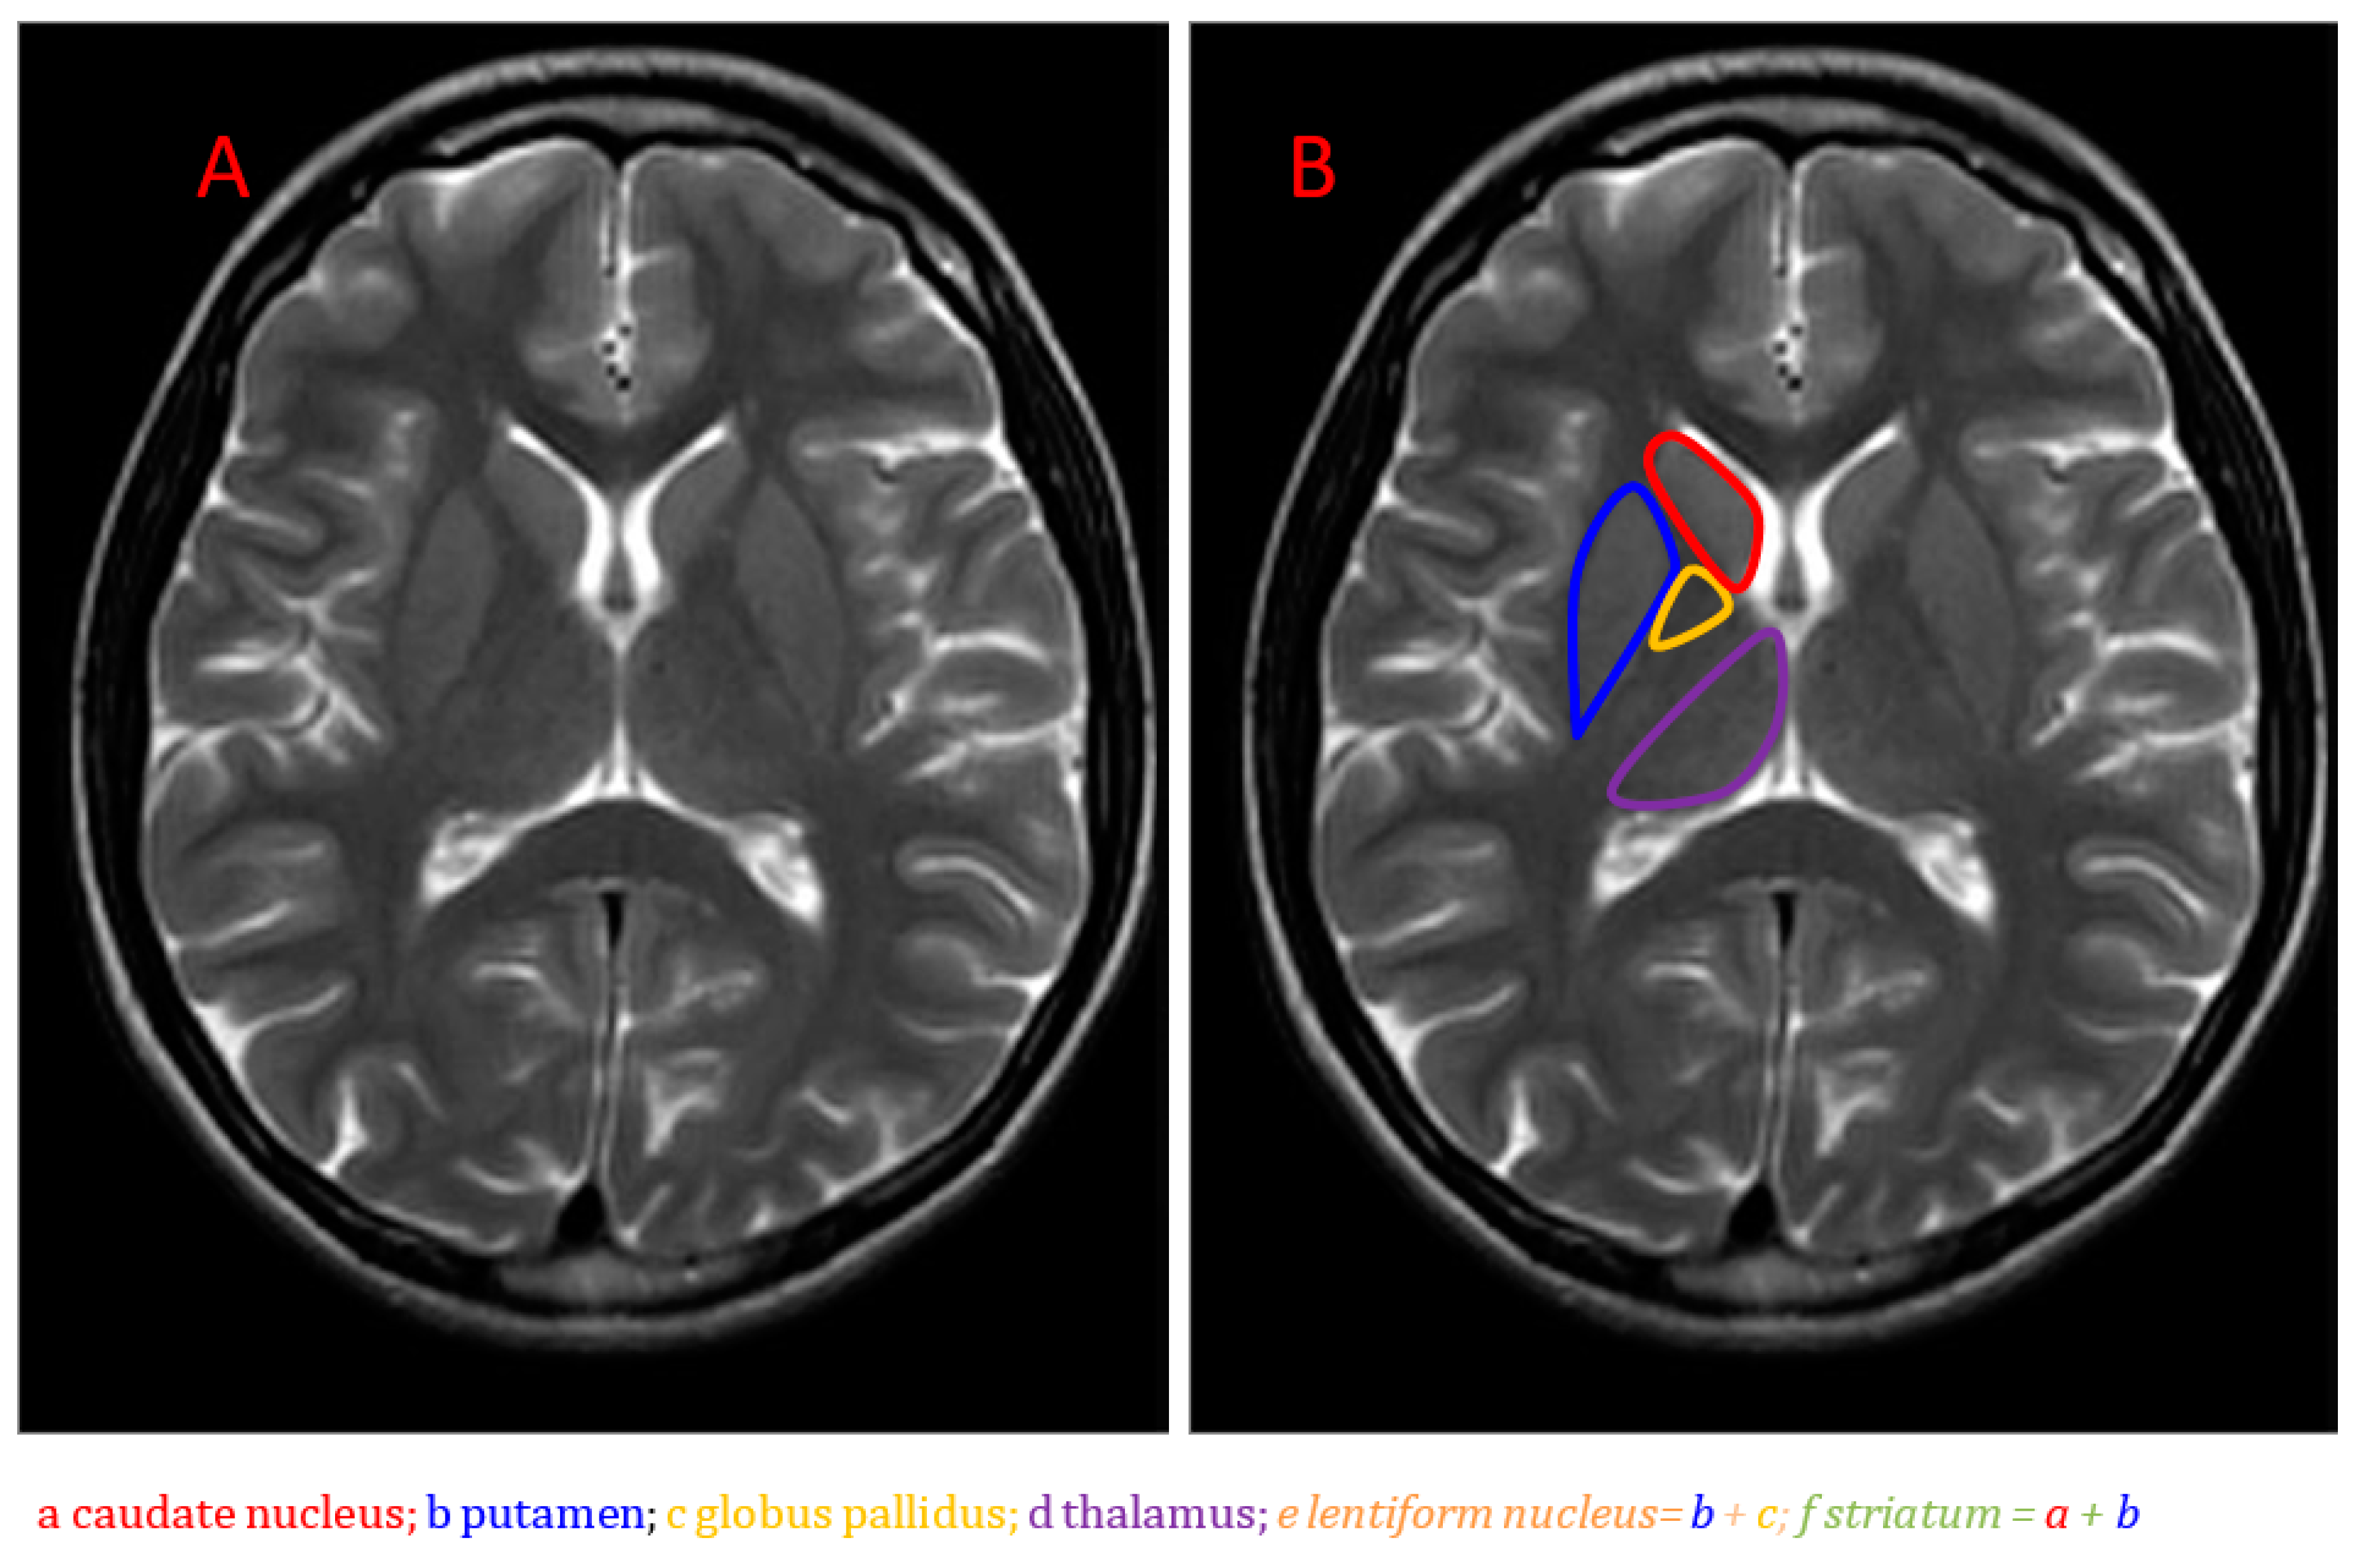

An Introduction to Neurometabolic Disease

Advances in next-generation sequencing and next-generation metabolic screening have greatly improved diagnosis and increased our understanding of neurometabolic diseases. Novel neuroradiology techniques, such as diffusion-weighted imaging and proton MR spectroscopy, are also increasing our understanding of the disease mechanisms. Gene therapy is starting to fulfil its potential in the treatment of some neurometabolic disorders.